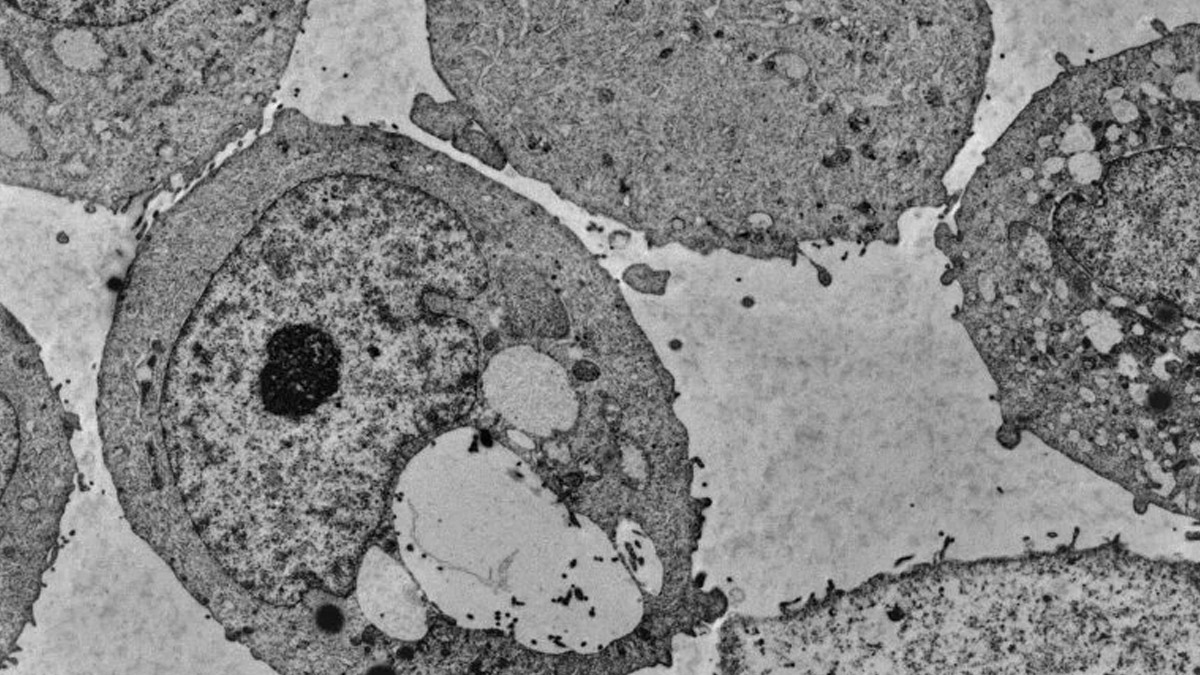

Led by Professor Elham Azizi, the study delves into how immune networks within the leukemia bone marrow microenvironment influence responses to cellular therapy. The central question of the research was: Why do some patients respond positively to immunotherapy while others do not?

The team discovered a distinct population of T cells present in patients who responded favorably to DLI therapy. These specialised cells actively combat leukemia by bolstering the patient’s immune response. Importantly, the study also revealed that patients with a healthier, more dynamic immune environment in their bone marrow were better equipped to support these cancer-fighting T cells.

The researchers traced the unique T cells back to the donor product but found that the donor’s immune cell composition played a negligible role in treatment success. Instead, the patient’s immune environment was the decisive factor. This discovery underscores the importance of optimising the patient’s immune landscape to improve therapy outcomes.